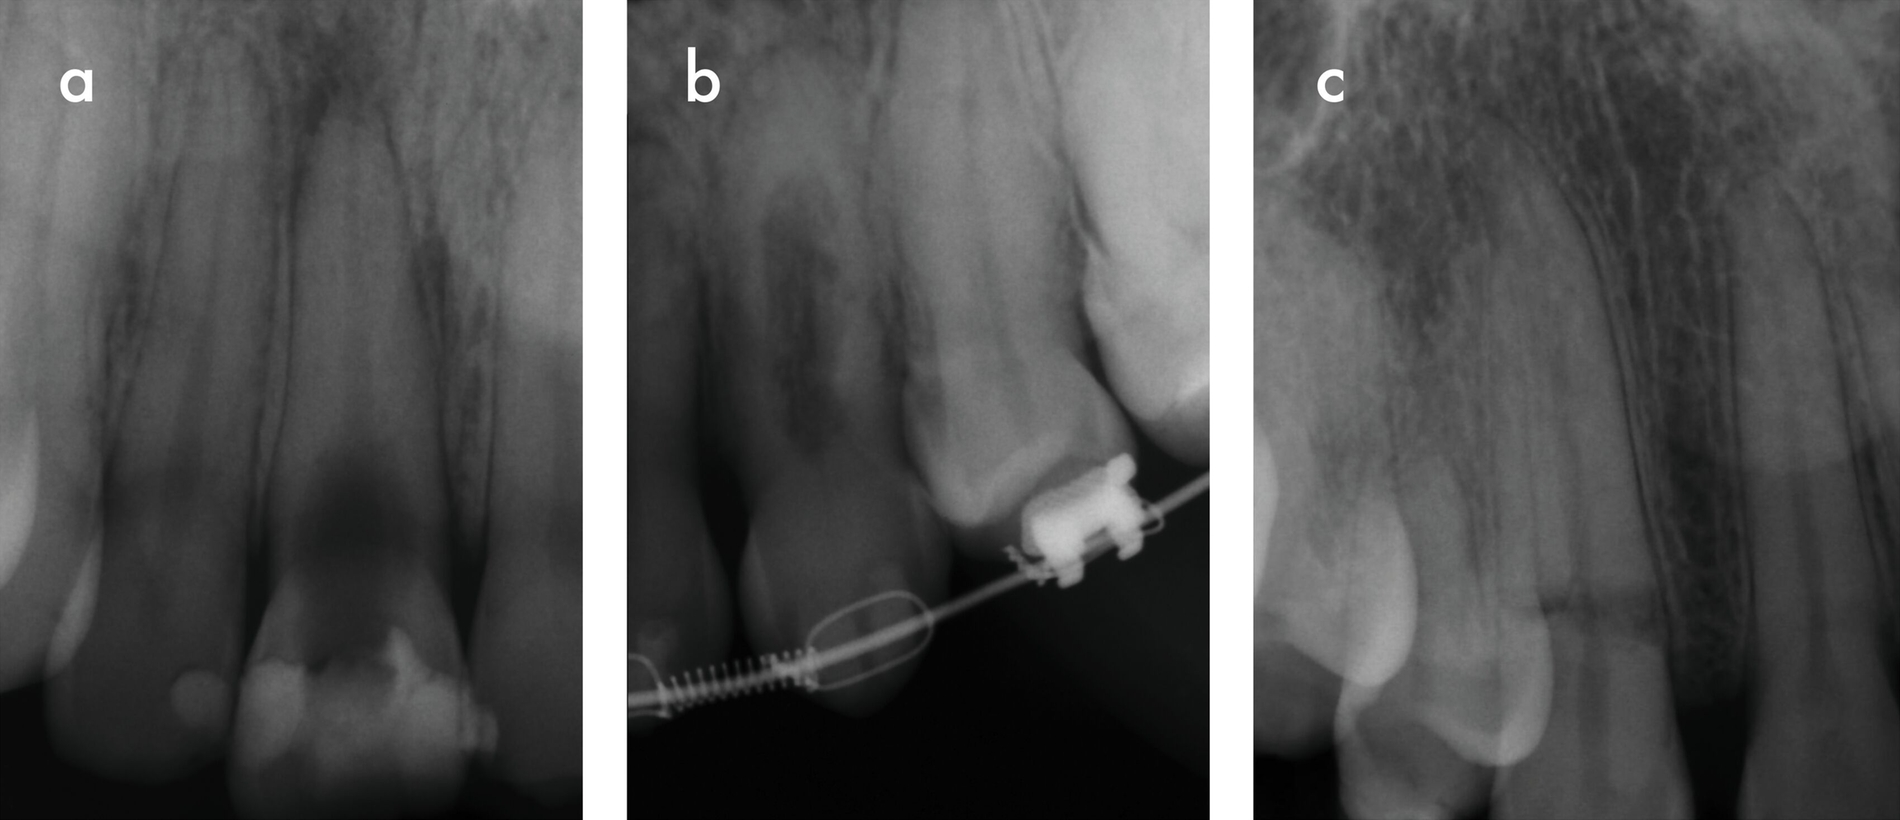

Die entzündliche Resorption wird durch Bakterien aus der nekrotischen koronalen Pulpa stimuliert und durch vitales Pulpagewebe apikal der Resorptionsfront aufrechterhalten (Abbildung 4a). Zusätzlich findet sich Granulationsgewebe im Inneren der Zahnwurzel. Wenn zusätzlich zu diesem Granulationsgewebe knochenähnliches Reparaturgewebe gebildet wird, spricht man von interner Ersatzresorption (Abbildung 4b). In beiden Fällen können je nach Pulpastatus Schmerzen auftreten. Radiologisch stellt sich die entzündliche interne Wurzelresorption meist als ovale oder zirkuläre, ballonartige Aufhellung des Wurzelkanals dar, während die Ersatzresorption ein unregelmäßiges, wolkiges und oft unscharf begrenztes Erscheinungsbild zeigt [Nilsson et al., 2013; Patel et al., 2010]. Es ist zu beachten, dass externe invasive zervikale Resorptionen (siehe unten) bei entsprechender Projektion häufig als interne Resorptionen fehlinterpretiert werden.

Eine Sonderform interner Wurzelresorptionen tritt im Rahmen von Reparaturvorgängen nach intraalveolären Wurzelfrakturen auf. Diese verlaufen häufig transient (Abbildung 4c). Eine klinische Symptomatik ist in der Regel nicht vorhanden, radiologisch lassen sich jedoch transiente Umbauprozesse entlang der Frakturlinie nachweisen [Andreasen, 2003; Andreasen und Andreasen, 1988].